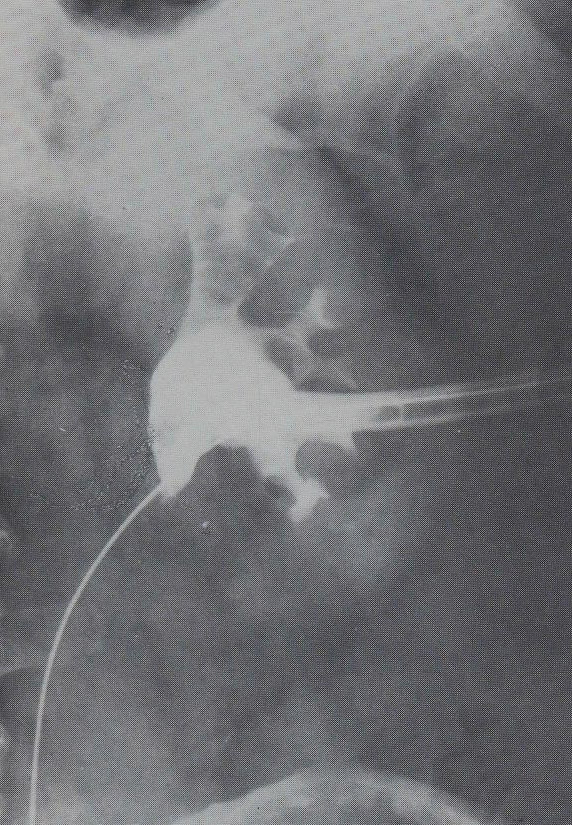

19.5.2. Percutaneous transhepatic drainage (PTD)

After a diagnostic PTC is successfully performed and a guide wire is positioned over the stenotic or occluded segment of the choledochal duct an external-internal drain (PTD) can be installed. (Figure 23.) If desired, a self expanding metallic stent could be used to override the stricture (Figure 24.)

Image

Figure 23. – PTD (Percutaneous transhepatic external-internal drainage)

Figure 24. – Choledochal stent, palliative procedure do pancreatic head tumor

If one cannot pass the biliary stenosis in the initial attempts, the placement of a temporary external drainage is advisory to control the biliary congestion and cholangitis. Later during a second session the insertion of an external-internal drain will be possible.